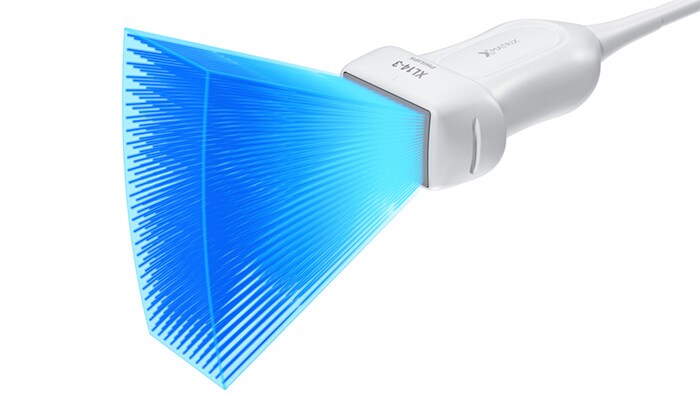

El primer transductor de array lineal xMATRIX del mundo

El transductor de array lineal XL14-3 xMATRIX para evaluaciones vasculares supone el mayor avance en 20 años de los ultrasonidos vasculares.

Array lineal XL14-3 xMATRIX

El transductor XL14-3 xMATRIX incorpora la impresionante cifra de 56 000 elementos, todos ellos conectados a un microcanal independiente. El transductor XL14-3 cuenta con enfoque electrónico multidimensional para adquirir imágenes de cortes ultrafinos de la anatomía vascular y la morfología de la placa. La ventaja principal: una excepcional de diagnóstico fiabilidad durante la evaluación de la estenosis y de la placa vulnerable.